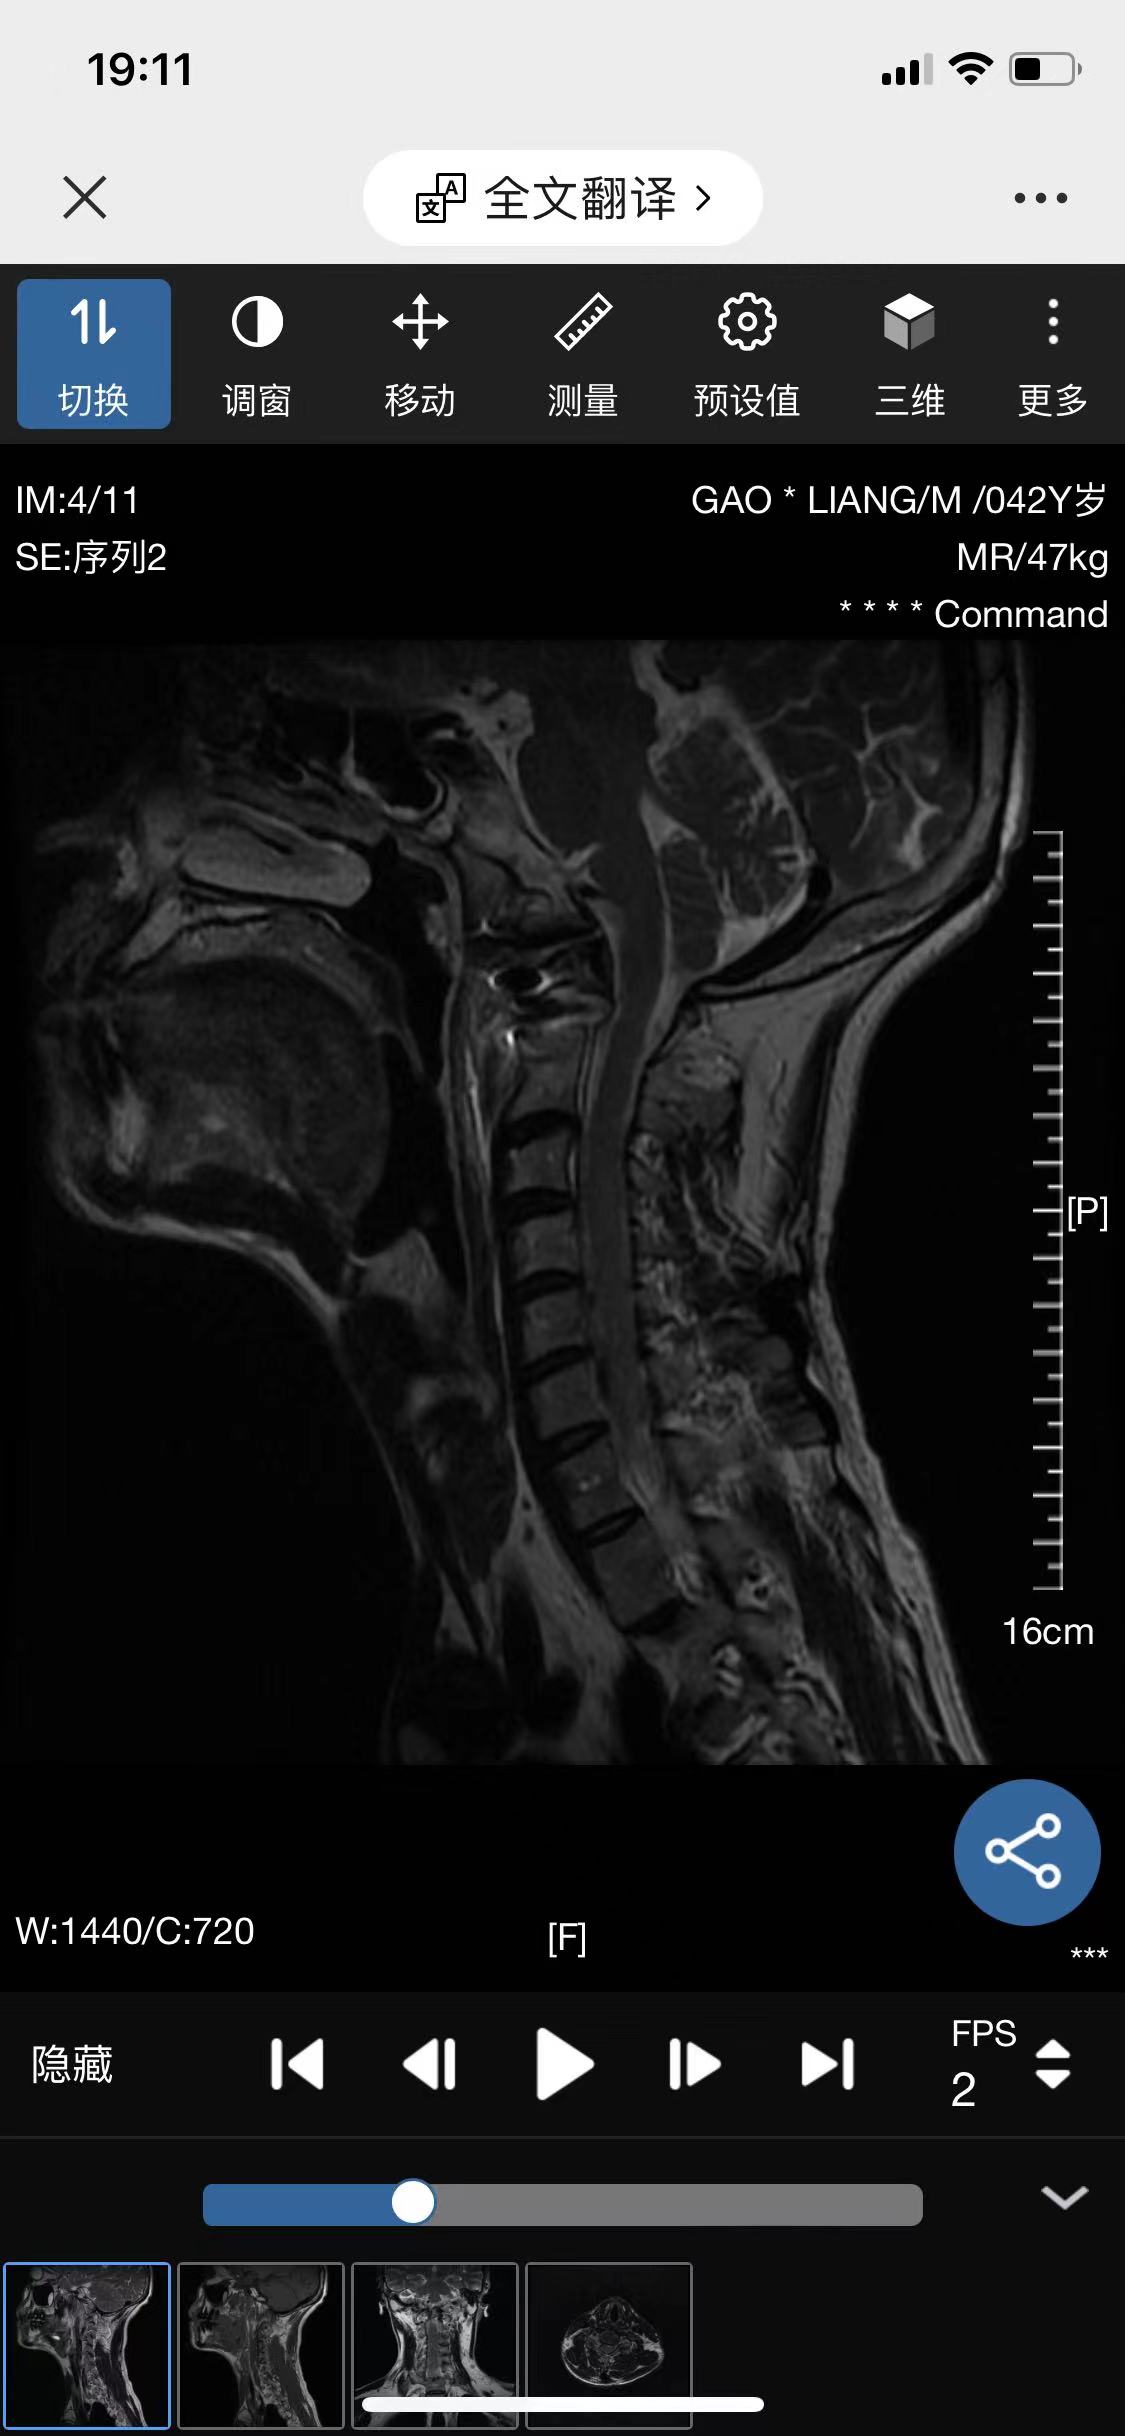

• 诊断:寰枢椎脱位

• 影像: